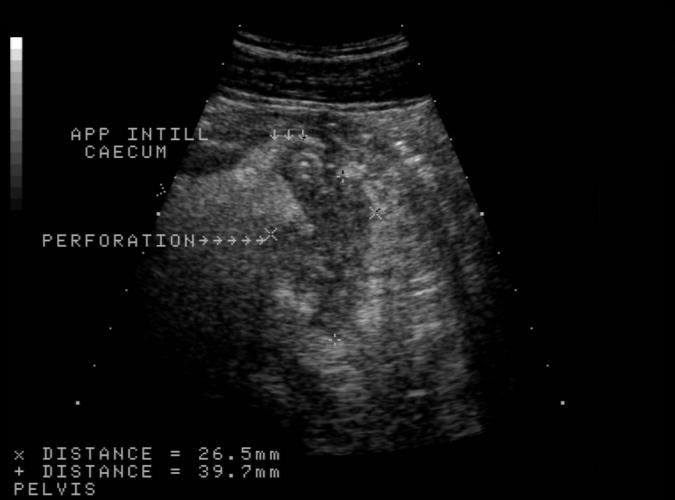

Trans. Blindtarmsinflammation med perforation.